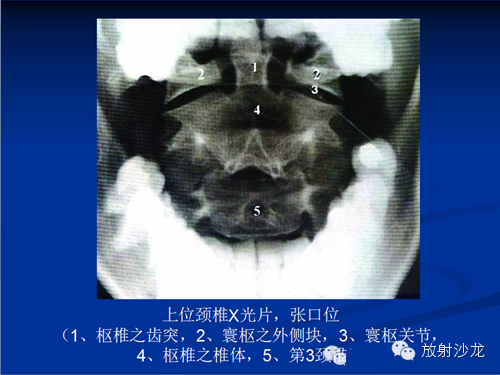

1.寰枢椎的判读